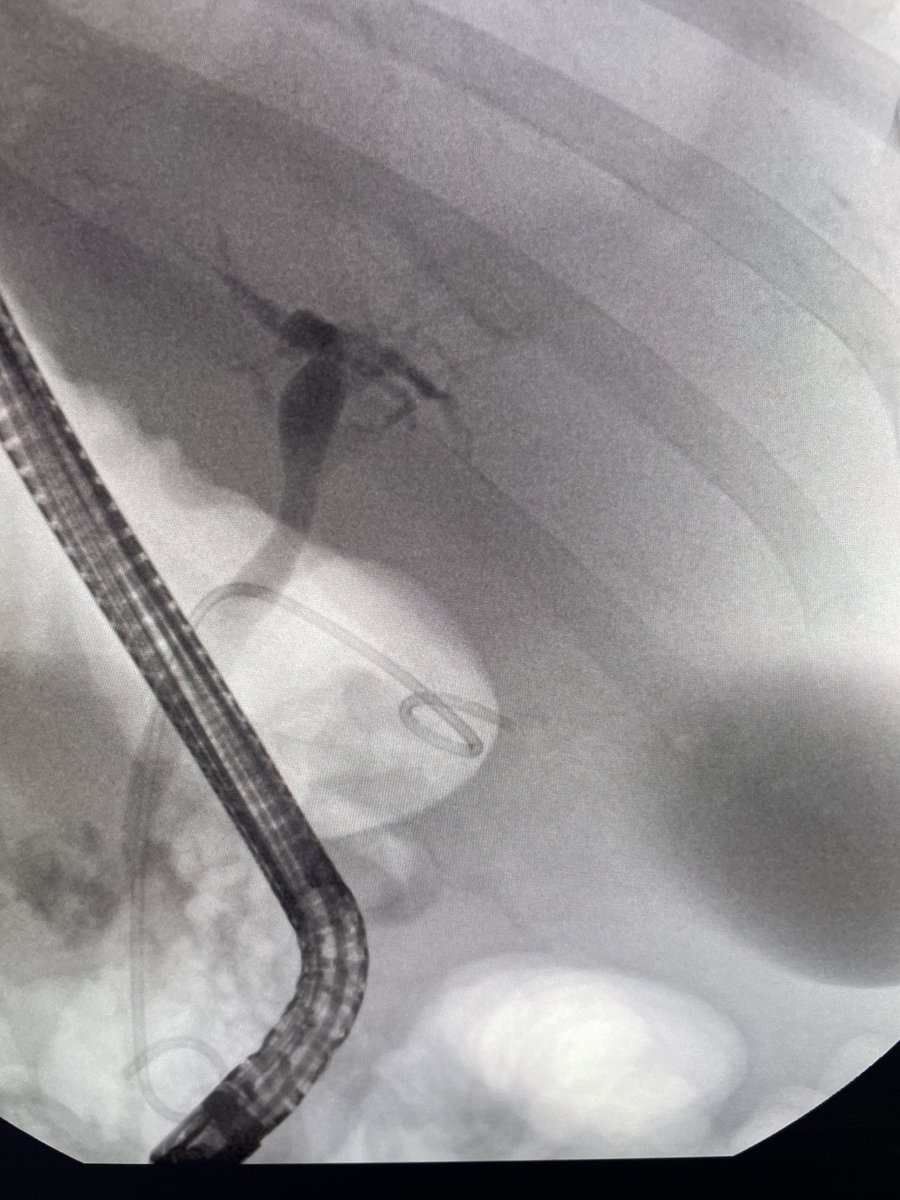

Another one. End stage liver disease with profound decompensation. Large ascites and severe coagulopathy. Acute cholecystitis treated with ERCP transcystic stent to very good effect. #gitwitter #liver #surgery @Stentingwoman ⁦@EUSandEndoscopy⁩